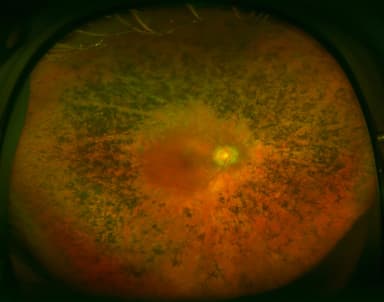

Viêm hắc võng mạc trung tâm thanh dịch là bệnh lý xảy ra khi dịch lỏng bất thường tích tụ ở phía sau võng mạc, đặc biệt tại vùng trung tâm – nơi quyết định thị lực rõ nét. Sự tích tụ này khiến võng mạc bị bong nhẹ, làm hình ảnh nhìn thấy trở nên mờ, méo hoặc biến dạng. Đây là bệnh mắt được đánh giá là tương đối lành tính, tuy nhiên nếu kéo dài hoặc tái phát nhiều lần vẫn có thể ảnh hưởng đến thị lực lâu dài.

3. Dấu hiệu nhận biết bệnh

Viêm hắc võng mạc trung tâm thanh dịch thường khởi phát âm thầm nhưng có thể gây ảnh hưởng rõ rệt đến thị lực trung tâm. Các triệu chứng giữa người bệnh có thể khác nhau, mức độ nặng nhẹ phụ thuộc vào thời gian mắc bệnh và số lần tái phát.

Những dấu hiệu thường gặp gồm:

- Nhìn mờ vùng trung tâm, thị lực giảm dần, thường ở mức khoảng 5/10–6/10; nếu bệnh tái phát nhiều lần, thị lực có thể suy giảm rõ rệt hơn.

- Hình ảnh bị méo hoặc biến dạng, đường thẳng nhìn thành cong, gợn sóng.

- Rối loạn cảm nhận màu sắc, đặc biệt là các gam màu sáng hoặc nhạt như vàng.

- Xuất hiện điểm tối hoặc bóng mờ che khuất tầm nhìn, thường nằm ở trung tâm hoặc cận trung tâm.

- Ám điểm trung tâm, có thể tự phát hiện bằng bảng ô vuông Amsler.